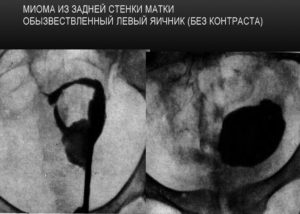

Миома, образовавшаяся на задней стенке матки

На ультразвуковом исследовании с влагалищным датчиком определяется размер опухоли, ее форма, наличие узлов. При проведении гистероскопии выявляется направление развития миомы, берется биопсия на гистологическое обследование.

В более редких ситуациях прибегают к проведению лапароскопического исследования, магнитно-резонансной и компьютерной томографии.

Естественно ультразвуковая диагностика, лапароскопическая, которая может переходить в лечебную при наличии показаний и отсутствии противопоказаний, ну и, конечно же, магнитно-резонансная томография и КТ.

При проведении диагностической лапароскопии или гистероскопии (миома матки на задней стенке матки, фото) обязательным является проведение биопсии для получения ткани с целью проведения гистологического исследования, для исключения онкологической патологии.